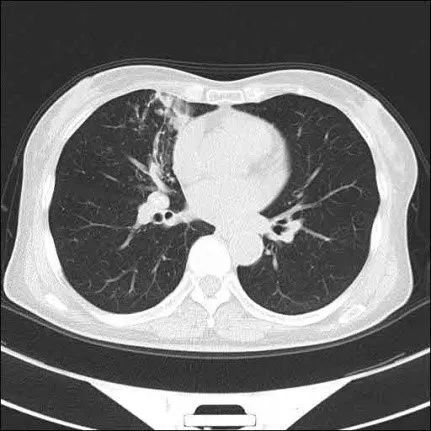

术前ct影像

完善术前准备后,结合胸部ct的大致定位,呼吸内科副主任医师在复杂的各级叶、段及亚段支气管中,顺利将支气管镜进入张奶奶的右中叶支气管,准确找到病灶位置。此时,在支气管镜下可以清晰地见到右中叶支气管粘膜充血水肿,内侧段上支有白色分泌物堵塞,在吸净后能看到右中叶内侧段粘膜糜烂,局部碳末沉积,触之易出血。在x线透视下,副主任医师精准地对右中叶内侧段上支处的病灶与内侧段上支开口处进行了活检、刷检及灌洗。术中患者未见并发症,术后安返病房。